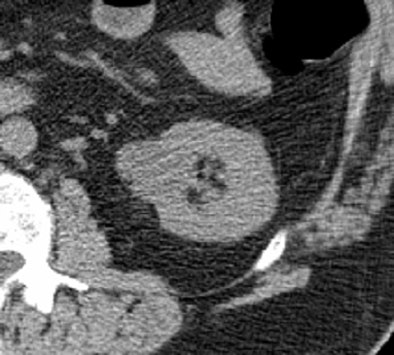

| Above, 3.5-cm left renal mass incidentally found at CTC of a 64-year-old man; further evaluation was recommended. Follow-up CT with and without contrast (below) demonstrated an enhancing mass. Patient underwent nephrectomy, and pathology was stage I renal cell carcinoma. The patient is still alive and without metastases, 4.5 years later. Images courtesy of Stacy O'Connor, MD. |